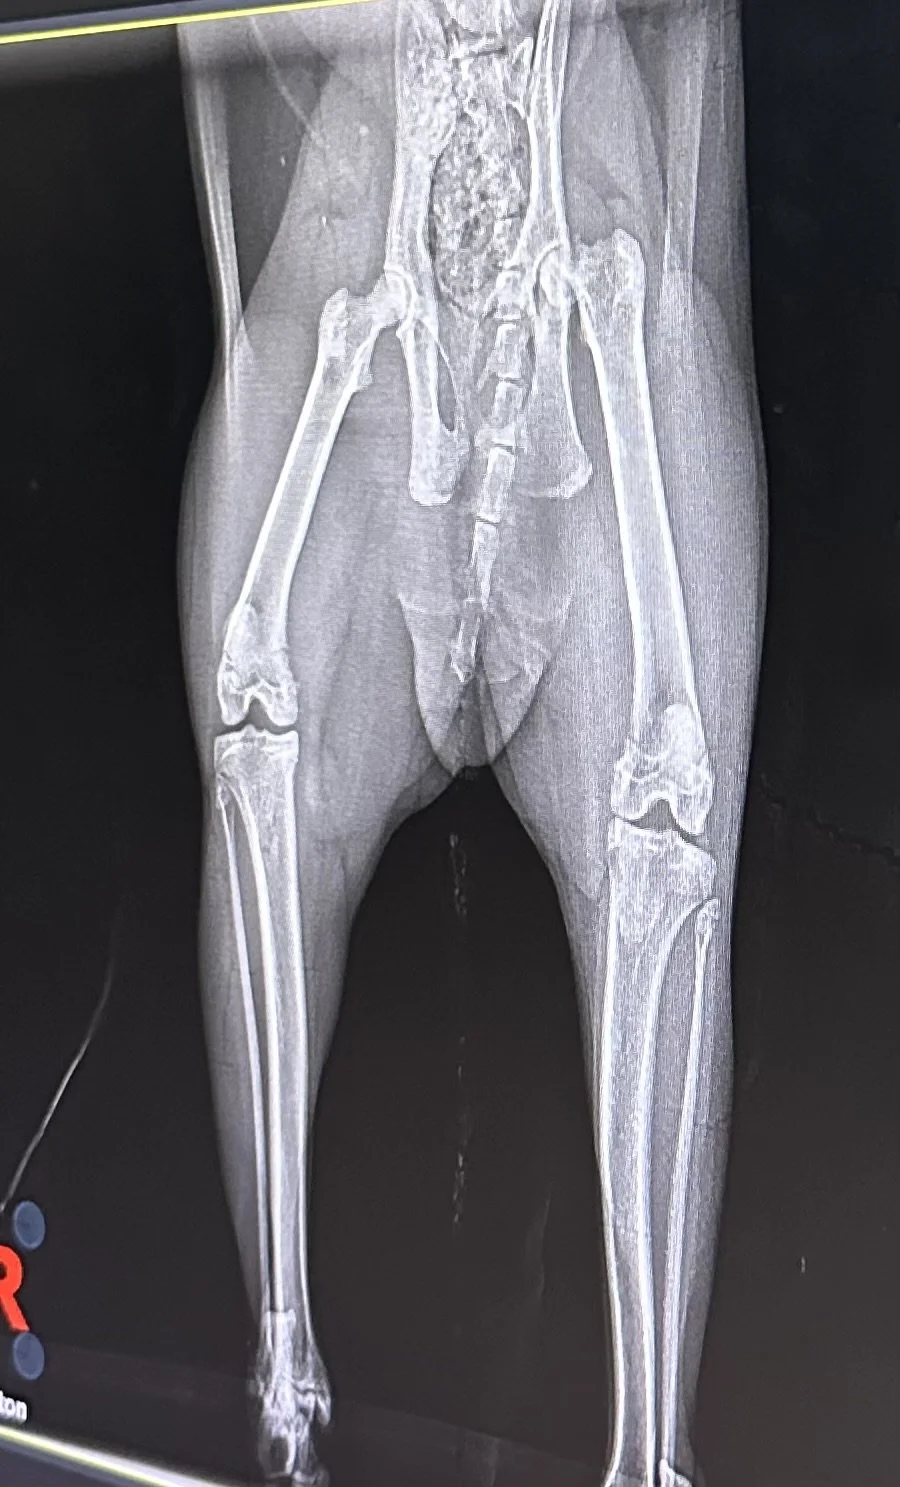

My cat broke her hip

It's late at night and I'm sitting here with Corina, who just had surgery this morning for a Femoral Head Osteotomy (FHO). She has Legg-Calvé-Perthes disease, which I found out about exactly a week ago. Seeing her hurt was genuinely scary.

She's resting now, still pretty loopy from the anesthesia. The vet said it'll be three months before she's moving normally, and a full year to completely heal. So I'm deep in cat mom mode, making sure my lil baby has everything she needs.